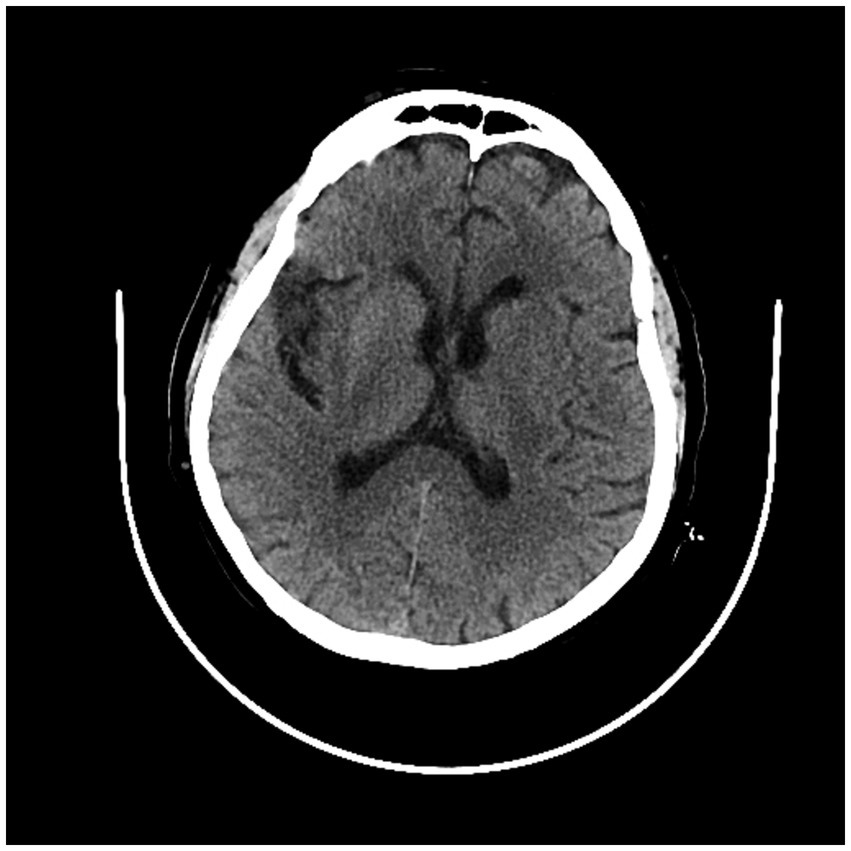

We found 12 patients with left IIS (80%) and only three patients with right IIS (20.0%). We detected 4/15 (26.6%) patients with anterior insular cortex lesion (AIC), 5/15 (33.3%) with posterior insular cortex lesion (PIC) and 6/15 (40%) with total insular cortex lesion (TIC). Eleven subjects (73.7%) had middle cerebral artery (MCA) involvement at CT angiography (CTA) (73.3%): 6/15 patients (%) had prevalent M1 segment occlusion, and 5/15 (33.3%) had prevalent M2 segment occlusion. The other four patients (26.6%) had no visible large vessel occlusion at CTA (Figures 3–5; Table 4).

Figure 3

CT scan showing left posterior insular cortex (PIC) ischemic lesion.